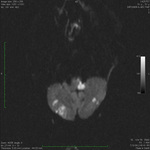

Infarto cerebelar bilateral agudo, observado na ressonância nuclear magnética de sequência de imagem ponderada por difusão

Do acervo de Dr. S. H. Subramony; usado com permissão